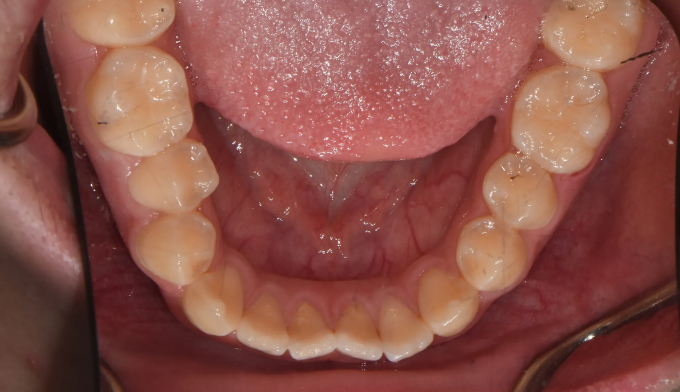

주걱턱 경향을 갖는 청소년들은 개방교합과 덧니를 동시에 갖는 경우가 많습니다. 아래턱의 과도한 성장은 혀의 위치를 아래로 처지게 만들고, 이는 위턱의 폭을 줄어들게 만들어 덧니가 생기기 쉽게 만듭니다. 그리고 과도한 아래턱의 성장은 앞니의 교합을 벌어지게 만들어 개방교합 또한 나타나게 됩니다.

그 정도에 따라 발치가 필요한 경우도 있지만, 성장기의 청소년의 경우에는 최대한 발치 없이 자연스러운 치열과 입매를 만드려고 합니다.

좁아진 위턱 악궁을 확장시켜서 치아를 배열시키고, 과도하게 앞으로 나온 앞니를 미니스크류를 이용하여 후방이동 시킵니다.